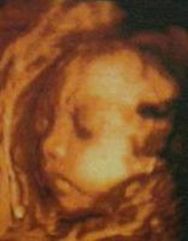

(3)立體顯像,動態直觀;可實時動態觀察胎兒頭部、軀體表面及內臟活動,圖像清晰精確可靠。

(6)可給胎兒拍攝精美的照片,錄下表情變化及刻錄光碟作為資料保存,留做永久的紀念。

妊娠的24~32周為妊娠中期,此時期可清晰顯示胎兒各部位臟器,了解胎兒生長發育情況,觀察頭、肢體及各臟器大體結構是否有畸形。由於該期胎兒發育完善、羊水量增多,三維成像在液性環繞的條件下效果更佳,可顯示大部分組織器官結構及整個胎兒發育狀況,該期胎兒面部豐滿,五官清晰,是診斷的最佳時期,成像成功率高,對臨床診斷最有意義。

彩超與三維彩超區別三維實時彩超不僅具有二維彩超全部功能,還具有其特殊功能立體成像、圖像切割、圖像鏇轉及高平面圖像分析。可以通過動態三維技術觀察胎兒在子宮腔內的活動及形態,能及早發現嬰兒畸形。三維彩超實現了人體局部組織器官的立體成像,可用於腹部及小器官的容積掃描,準確測量局部組織器官,如通過檢查胎兒頸背部皮膚及測量皮下組織的厚度,可以在懷孕9—13周期間發現遺傳性(染色體)畸形。三維彩超突出的特點是可拍攝到不同孕周的胎兒在宮內生長發育的局部立體圖像,從三維畫面中可清晰看到宮內沉睡胎兒的左耳和小拳頭以及面部生動鮮明的表情。